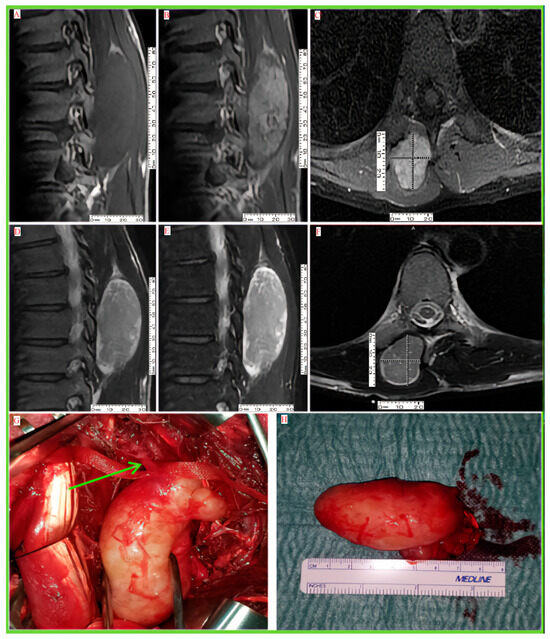

| Imaging findings | Well-defined ovoid lesion. Hypointense T1W. Heterogeneous enhancement | Well-defined lobulated lesion. Heterogeneous low signal intensity on T1 and high signal intensity on T2W. Heterogeneous enhancement | Fascicular bundle revealed by hypointense foci within hyperintense area on T2W | Heterogeneous T1 and T2W high signal intensity. Peripheral irregular heterogeneous contrast enhancement with central non-enhancement | Well-circumscribed lesion. Hyperintense T2W. Hypointense T1W. Peripheral contrast enhancement with necrotic center | Well-circumscribed lesion. Hyperintense periphery on T2W and hypointense in center. Hypointense T1W. Peripheral contrast enhancement with necrotic center | Well-circumscribed lesion. Hyperintense periphery on T2W with target signs, hypointense in center. Hypointense T1W. peripheral contrast enhancement with a necrotic center | Ultrasound superficial heterogenous soft-tissue mass (9.09 × 7.01 cm.). Large soft-tissue mass with hypervascularity on MRI. Multiple satellite lesions of varying dimensions on CT | Well-circumscribed lesion. Hypointense T1W. Hyperintense heterogenous cystic components on T2W. Peripheral contrast enhancement of solid component. Identified entry/exit nerve |